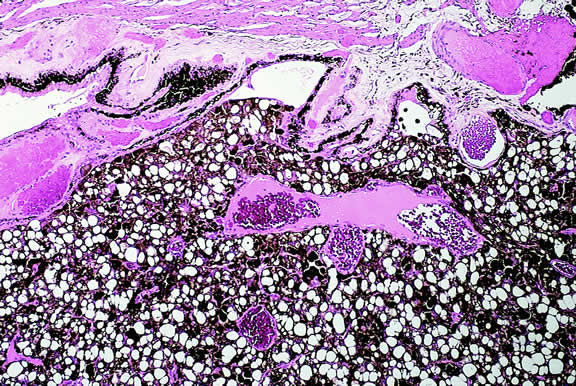

Macroscopically, the appearance of eyes with uveal metastases is somewhat variable. In most instances the uveal tract is diffusely thickened by an infiltrate of white, pink, or yellow tissue (Fig. 50). Metastases occasionally have a multinodular growth pattern, and a few larger lesions are oval in configuration (Fig. 51). Bruch's membrane almost always remains intact, however. Although there are exceedingly rare exceptions to the rule, one generally can conclude that a mushroom-shaped tumor of the choroid is a malignant melanoma.

Fig. 50. Uveal metastasis. Uveal stroma in enucleated eye is diffusely thickened by focally hemorrhagic infiltrate of metastatic tumor.

Microscopically, the uveal stroma is infiltrated by nest, cords, islands, and sheets of tumor cells whose general appearance and arrangement is dependent on the identity of the primary neoplasm. Most of the breast and lung tumors that metastasize to the eye are mucous-secreting adenocarcinomas. In such cases special stains such as Alcian blue, PAS, or mucicarmine are used to demonstrate the presence of intracytoplasmic mucin (Fig. 52). In most instances the pathologist can readily distinguish between a primary uveal melanoma and metastatic carcinoma in routine sections. Immunohistochemistry may be helpful in exceptional cases. Carcinomas are distinguished by positive immunoreactivity for epithelial markers such as cytokeratins and epithelial membrane antigen. Most melanomas stain with S-100 protein and vimentin and a variety of other markers including so-called melanoma specific antigen HMB-45, melan A, and microphthalmia factor. Occasionally, immunohistochemistry can confirm or provide clues to the identity of the primary tumor by demonstrating the presence of tumor specific antigens such as prostate specific antigen (PSA) in prostatic carcinoma or thyroglobulin in thyroid. Distinguishing between a primary uveal melanoma and choroidal metastasis from skin melanoma or another primary nonocular pigmented neoplasm may be challenging.197,198

Fig. 52. Mucin-secreting adenocarcinoma metastatic to the uvea. Alcian blue stain highlights mucin vacuoles in nests of tumor cells. (Alcian blue, × 100.)